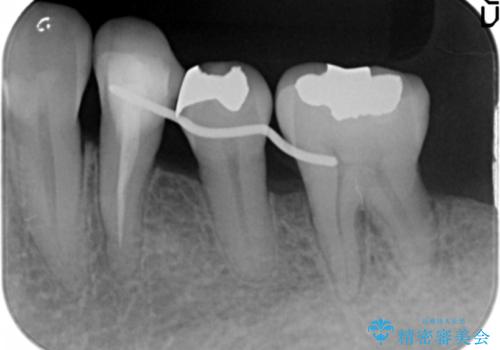

- 全顎的な重度歯周病の患者様です。

骨吸収の進行している左下臼歯部に、再生療法(骨を増やす手術))を行いました。

再生療法から1年後、リエントリー手術により骨の再生を確認し、骨外科処置(骨を平らにして歯周ポケットの根本的な改善を図る処置)を行いました。

埋伏していた親知らず、保存不可能な左下の一番奥の歯(左下7)は抜歯しました。